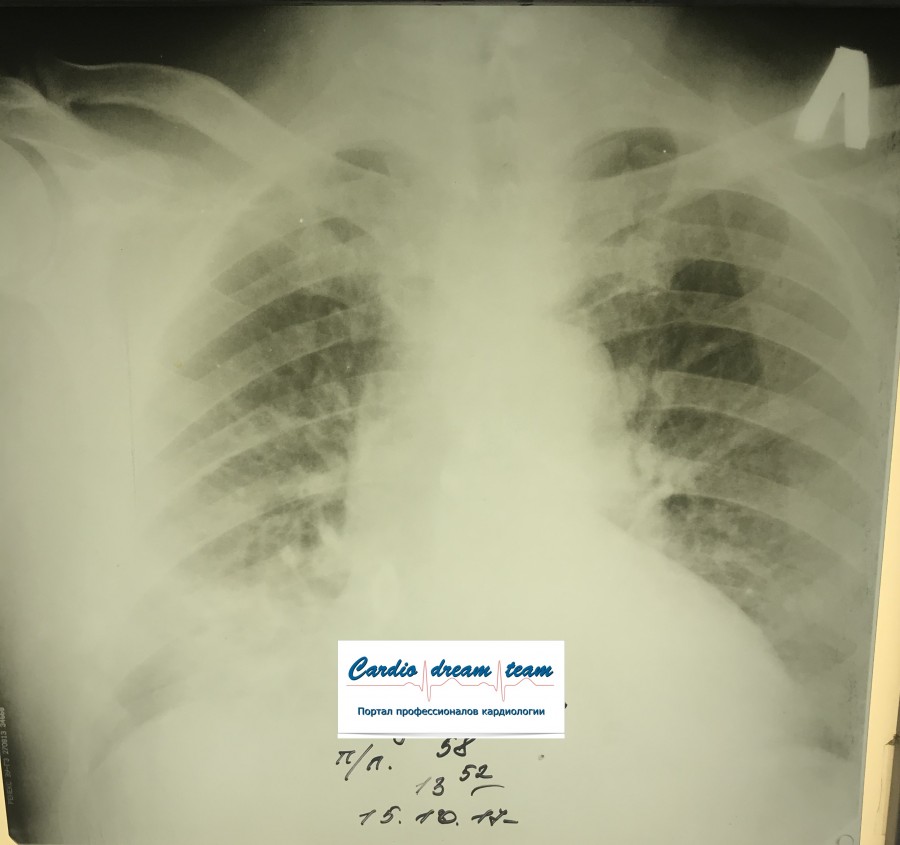

Двухсторонняя пневмония

Вложения:

IMG_0886.png

IMG_0886.png [ 759.15 KiB | Просмотров: 23128 ]

IMG_7045.png

IMG_7045.png [ 782.71 KiB | Просмотров: 23128 ]

IMG_7003.JPG

IMG_7003.JPG [ 121.75 KiB | Просмотров: 23128 ]